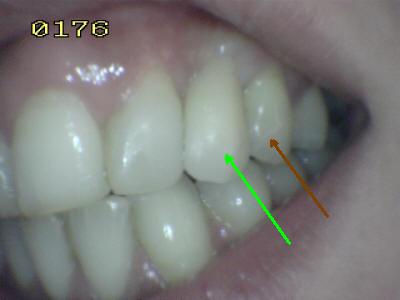

| Para el tallado de los dientes es

indispensable la reducción de los contactos dentarios antagonistas en

habitual y excéntrica. En la imagen inferior se muestra la forma

correcta de hacerlo. Esta maniobra reduce el cingulum en una angulación

de menos de 90º. Necesario para que nuestra prótesis no se deslice

y despegue. |